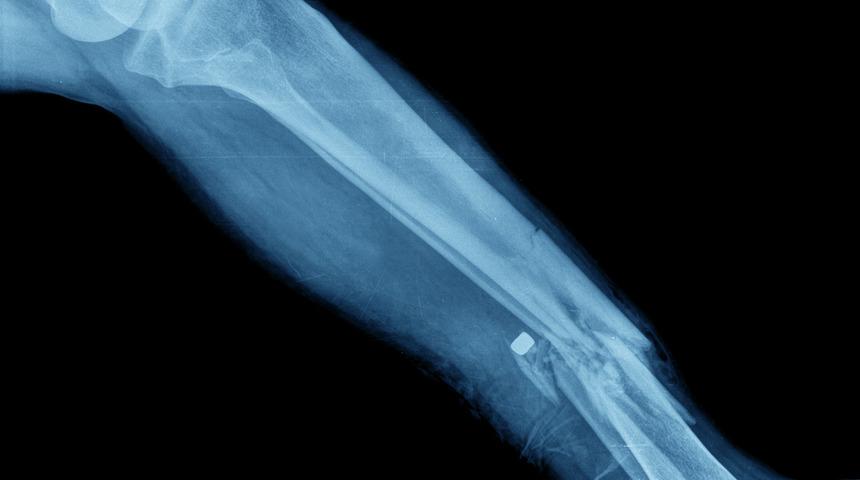

İtalya'da kolluk kuvvetleri, insanların kemiklerini doktor kontrolünde kırdıktan sonra araba kazası numarası geçirdiklerini söyleyerek sigorta şirketlerinden milyonlarca euro tazminat almakla suçlanan 34 kişiyi gözaltına aldı.

50'den fazla kişinin apartmanlarda veya depolarda ayarlanan mekanlara götürülerek anestezi verildikten sonra büyük taşlarla kol veya ayaklarının kırıldığı açıklandı.

Çete üyeleri ayakları kırılan kişileri yakınlarıymış gibi hastaneye götürdü.